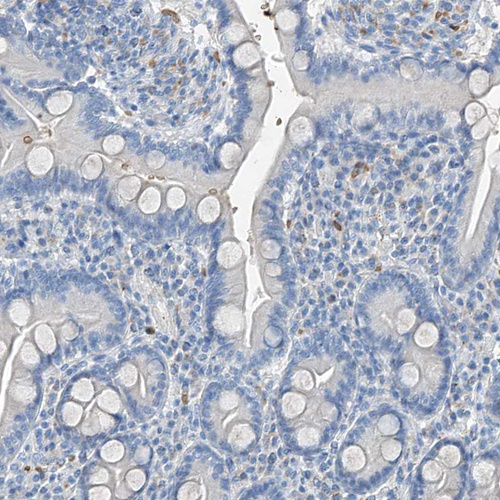

Immunohistochemical staining of human placenta shows moderate cytoplasmic positivity in trophoblastic cells.